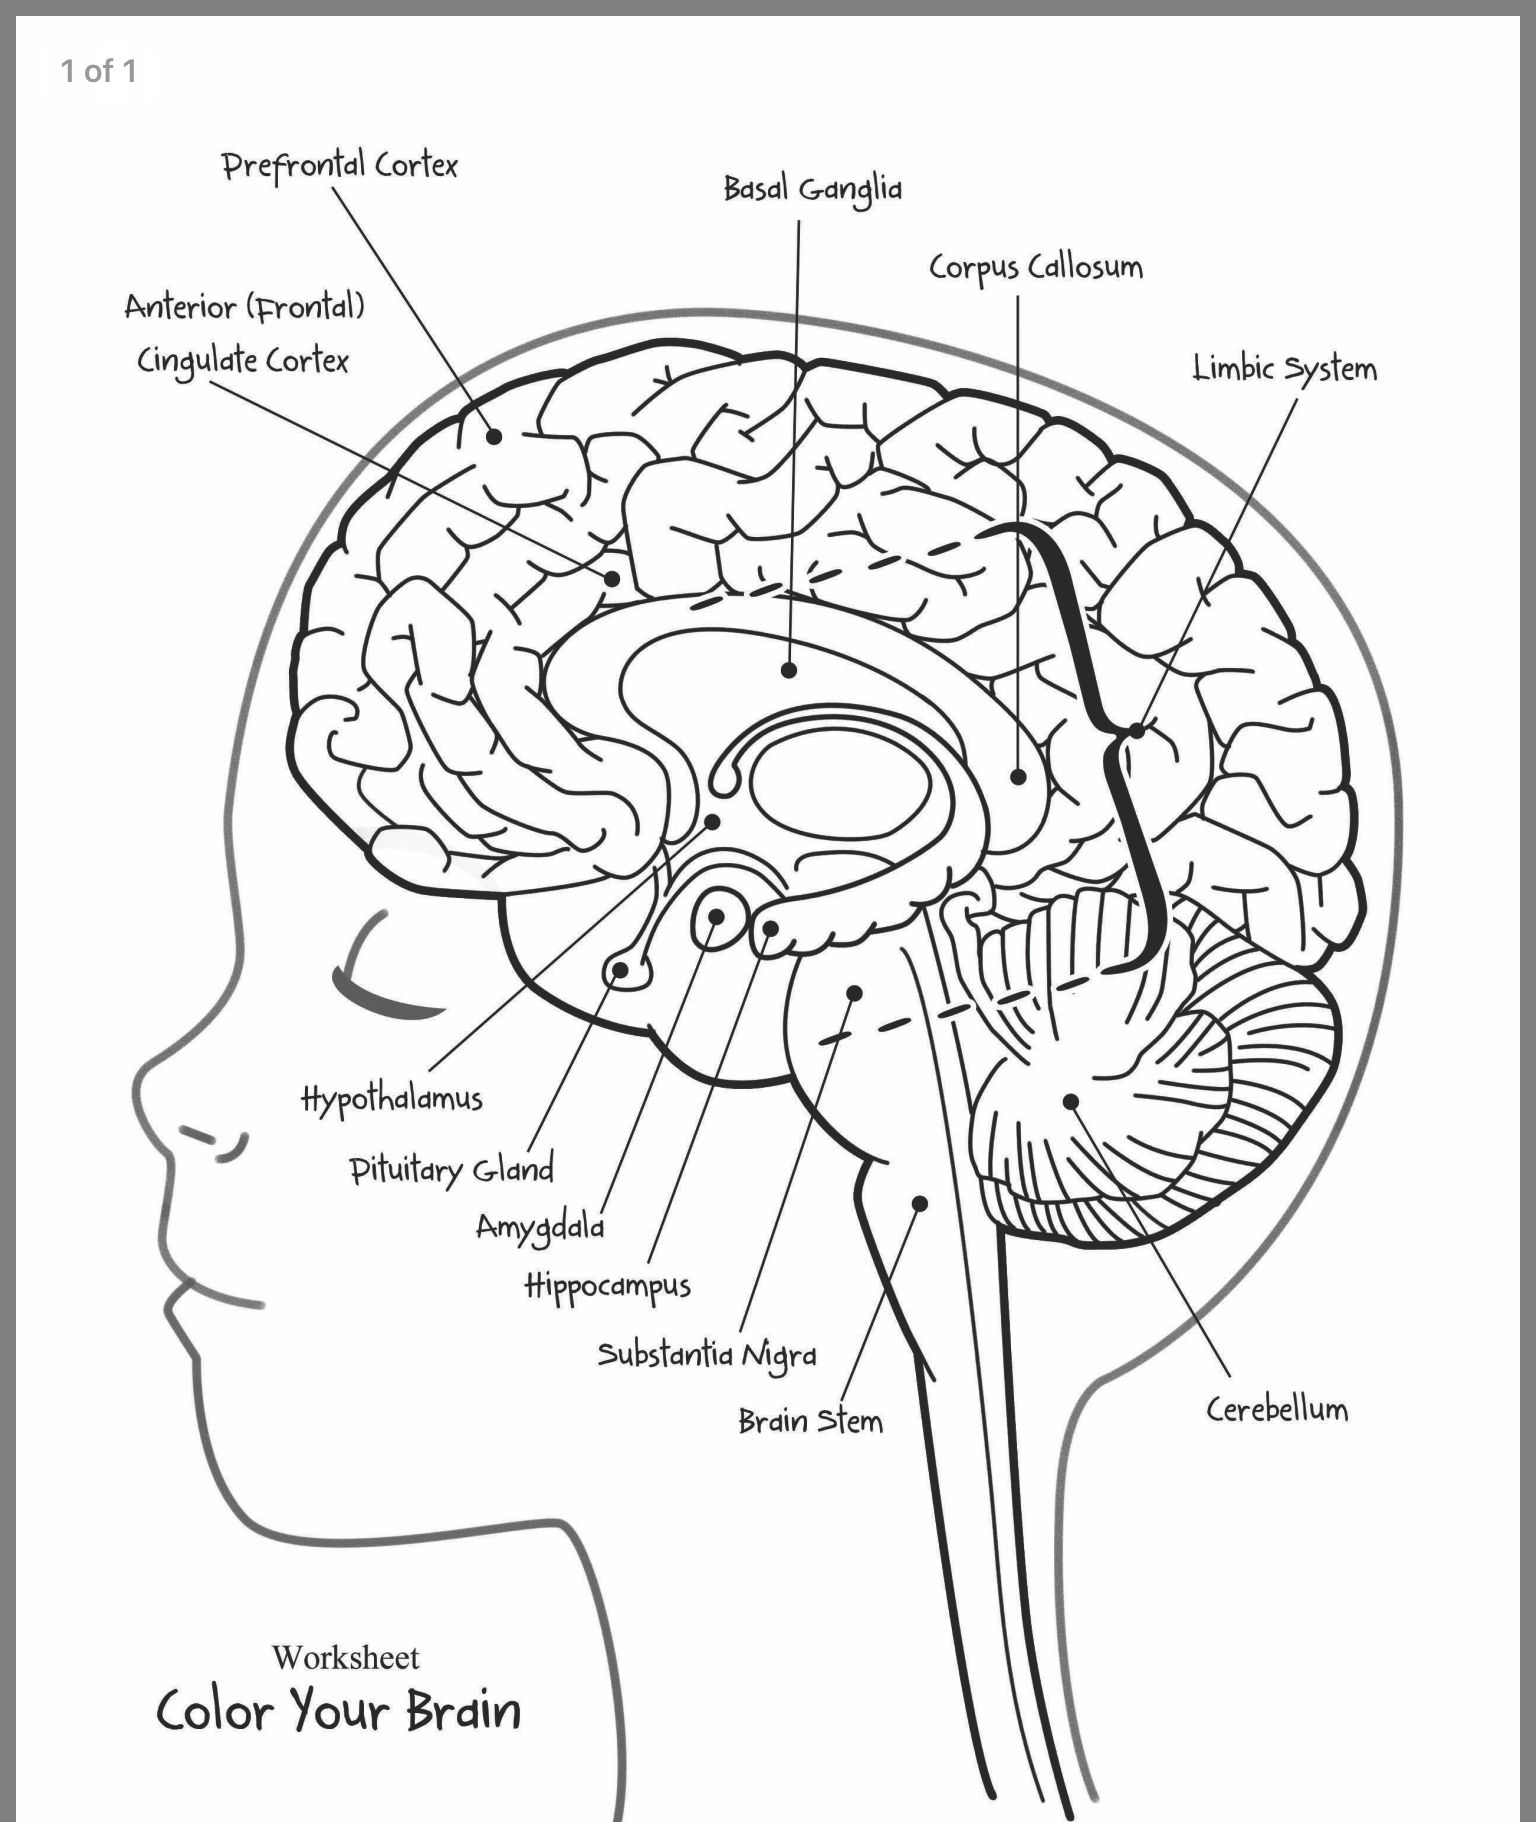

Human Brain Anatomy Worksheet

Human Brain Anatomy Worksheet

For a enjoyable method to strengthen finding out concerning the human body, you can make use of Human Brain Anatomy Worksheet. Some of them have labels to make it simple to determine components of the body.

Some of the human body worksheets are offered for homeschooling. You can utilize them to teach children the names of all the organs, and their proper placement. There are additionally vocab lessons and also writing sentences to help your youngsters exercise the new details. You can also use these worksheets for science lessons.

Another enjoyable task for children is the body project. The worksheet includes various body systems, such as the skeletal system, the muscle mass, and also the mind. There are also tracing documents that children can make use of to cut as well as trace out parts of the human body. You can additionally allow your child enhance the body with various clothes.